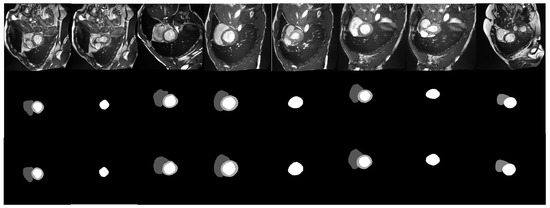

As shown in Figure 6, the comparison between the proposed method and its baseline models (nnU-net and TransUNet) on ACDC dataset is presented. It can be seen in Figure 6 that the performance of nn-TransUNet is favorable compared to its baseline model. In the first and second row, the segmentation maps that nn-TransUNet generated are the most similar to the ground truth images, especially on the LV (Left Ventricle) part. It indicates that the segmentation accuracy of nn-TransUNet is better than that of nnU-net and TransUNet. In the third row, the difference between the segmentation maps of nn-TransUNet and nnU-net is not obvious except that the edges of each segment presented by nn-TransUNet tend to have more details than their counterparts presented by nnU-net. But both methods are significantly better than TransUNet, which had false positive results in its predictions. It shows that the experiment planning pipeline implemented in the proposed method can reduce the network error rate. In summary, by combining the TransUNet network with the automated experimental planning pipeline of nnUNet, nn-TransUNet prevails in the comparison to its baseline models. It also reveals that a proper training and preprocessing plan can boost the performance of a network model even when its performance is already good, which is the starting intuition of this paper.

Figure 6.

Qualitative evaluation of different methods by visualization.